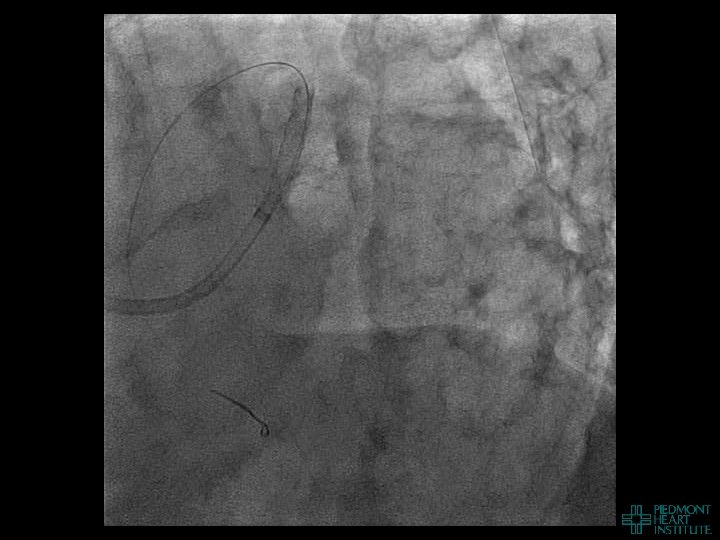

Coronary Perforation Methods of Patient Management • Dual Catheter (‘Ping Pong’) Technique • Prolonged

Coronary Perforation Methods of Patient Management • Dual Catheter (‘Ping Pong’) Technique • Prolonged balloon inflation and covered stents • Reversal of anticoagulation — Know contradictions to protamine sulfate for UFH; Avoid bivalirudin, LMWH — Reserve GP 2 b 3 a inhibition until successful crossing and wire change-out Embolization • — Coil, gelfoam, methacrylate, autologous blood/fat • Microcatheter Occlusion • Confirmation of successful management — Contralateral injection — Right heart catheterization — Echocardiogram — Contrast echocardiography